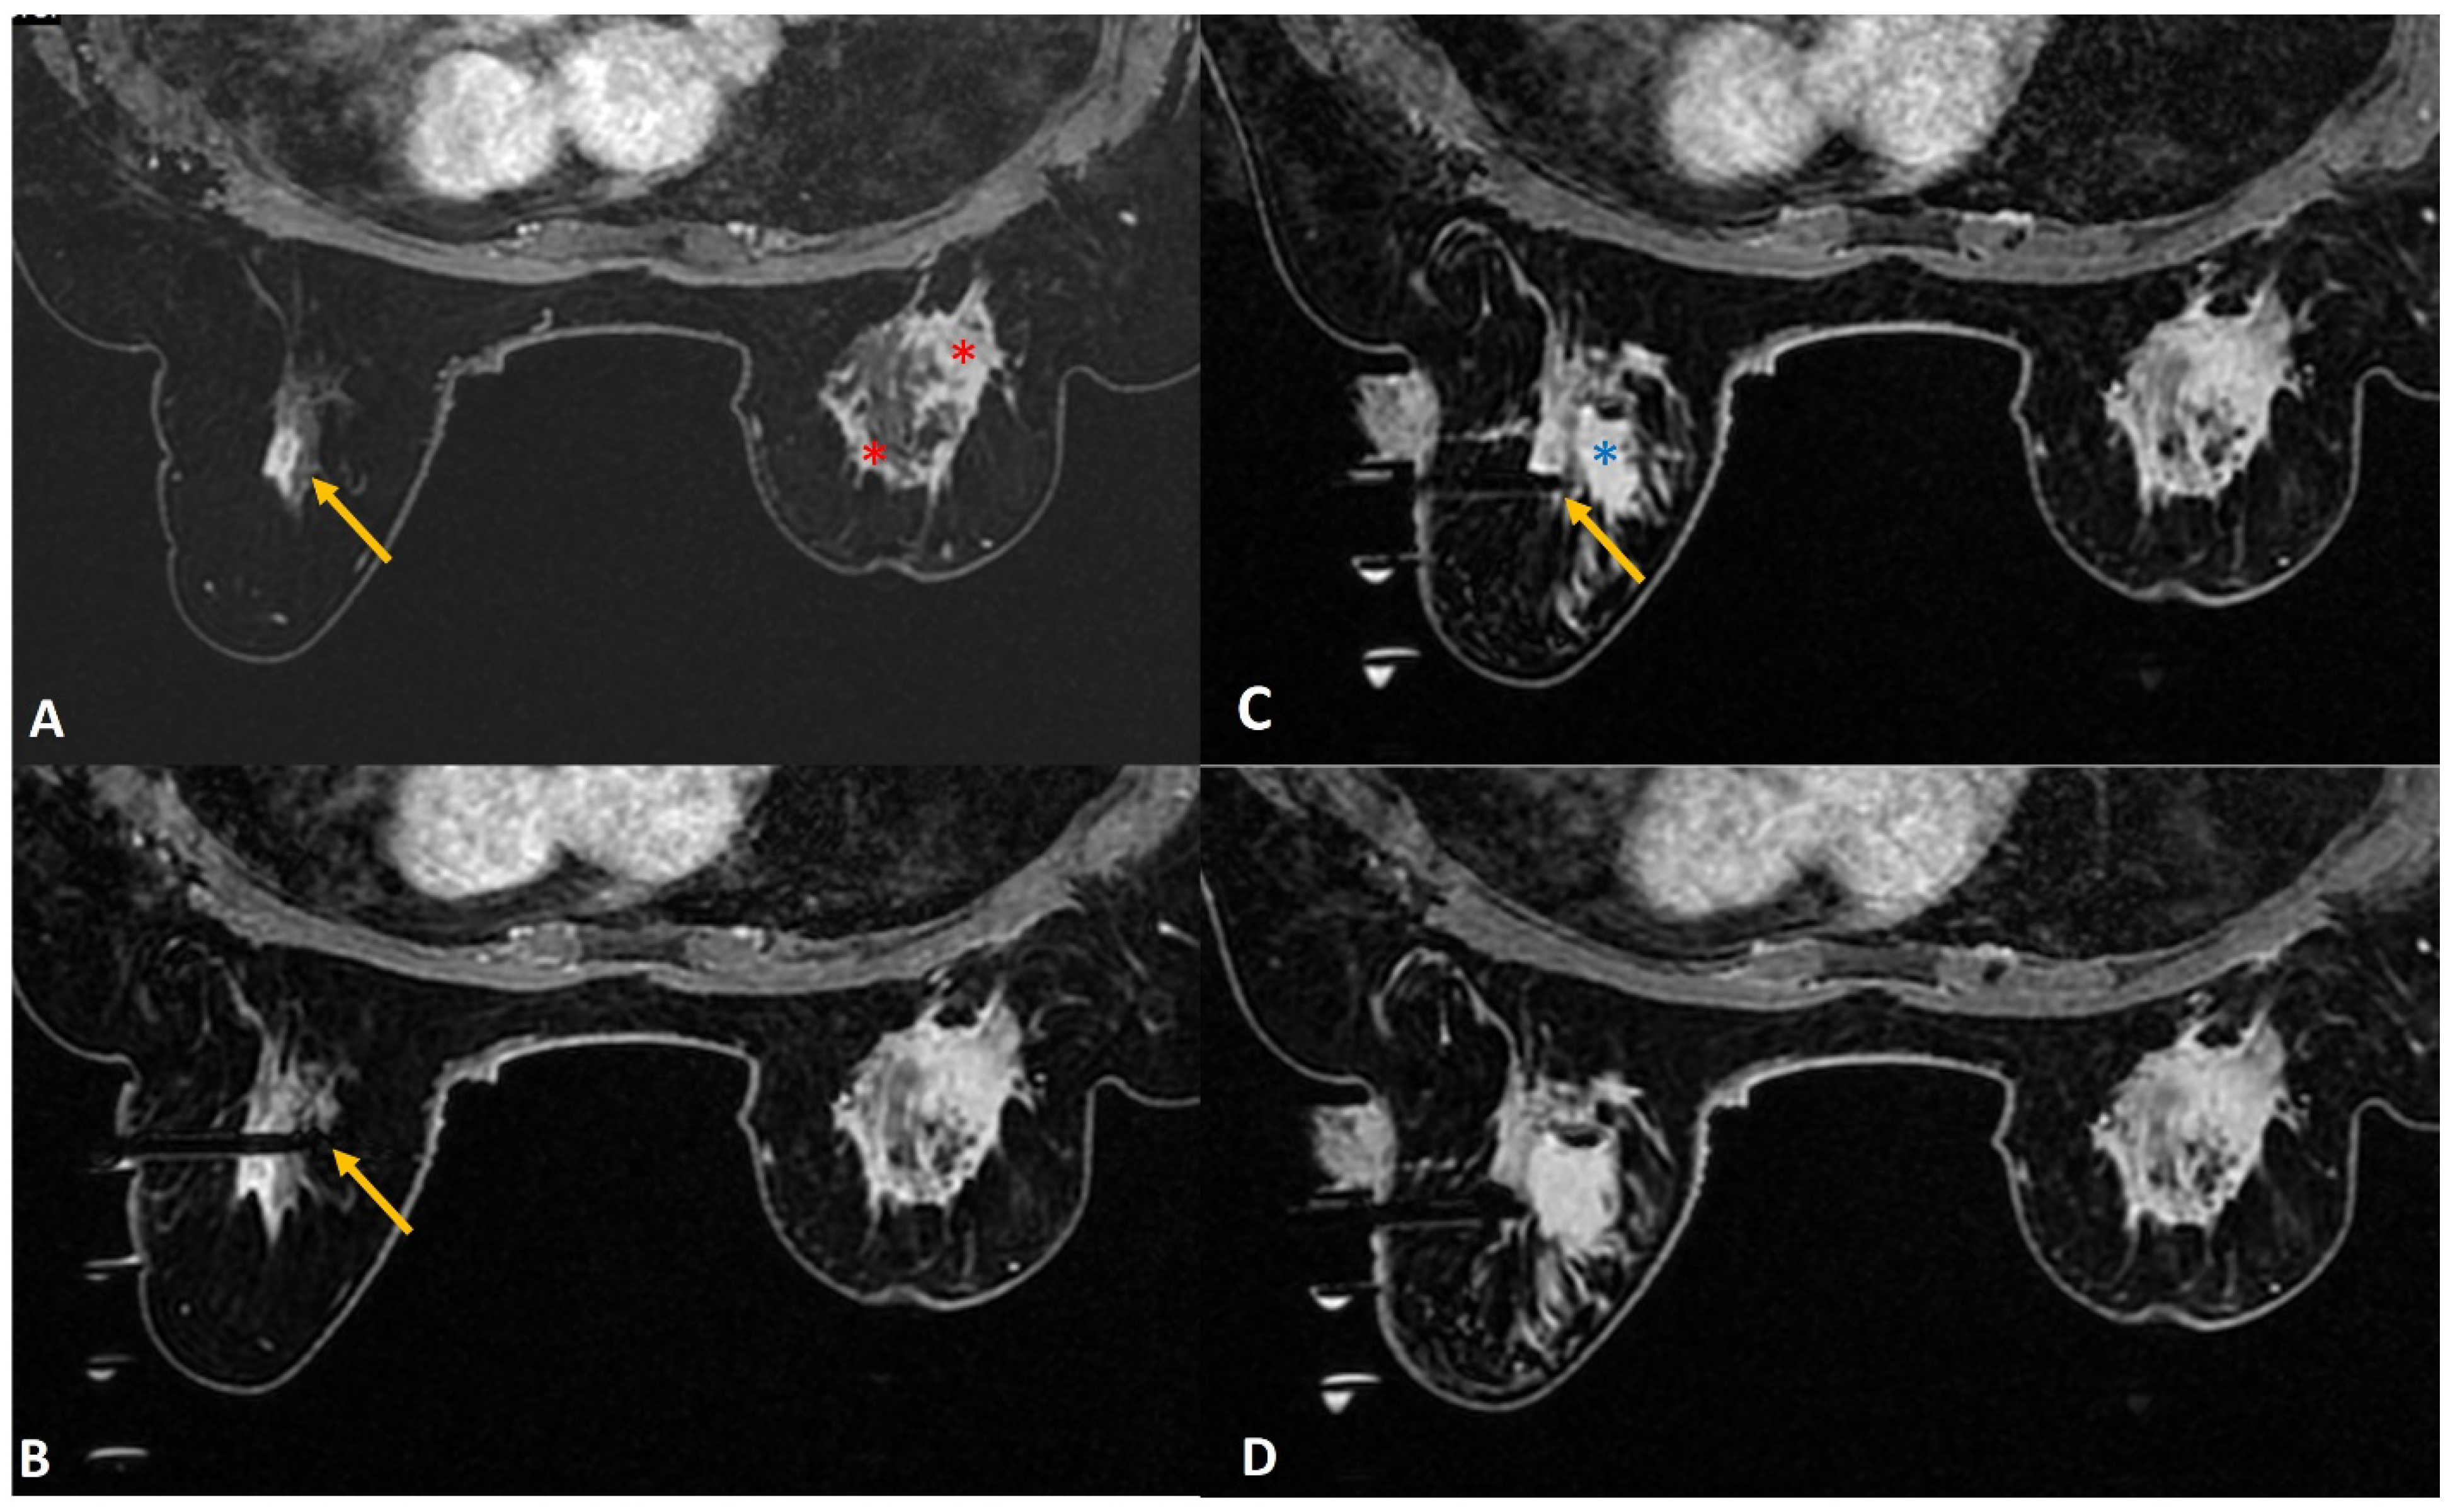

Figure 1.

A 36-year lactating mother diagnosed with left breast inflammatory breast cancer underwent staging MRI. (A). Sagittal post contrast T1w fat-saturated image showed a segmental non-mass enhancement (yellow arrows) in the upper outer quadrant of the right breast. This was also distinctly FDG avid on PET scan (not shown here). (B). Axial staging scan showed diffusely enhancing mass in the left breast correlating with known cancer (red asterisks). Segmental non-mass enhancement was also seen in upper outer quadrant of the right breast (yellow arrow). (C). MRI-guided biopsy shows the tip of the obturator in correct location with surrounding post-biopsy hematoma (yellow arrow). Histology was reported as fibrocystic change.